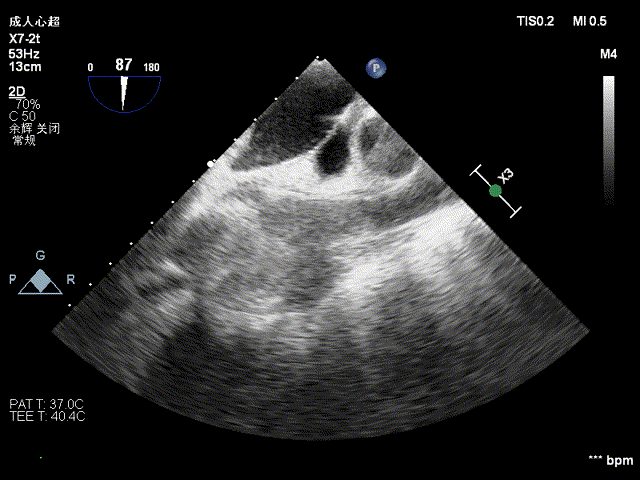

经心尖TAVR

主动脉根部造影后,介入器跨瓣:

定位件进入窦部:

将瓣膜件降至合适水平面:

释放瓣膜后,复查根部造影,未见明显反流,瓣膜形态和位置满意,双侧冠脉显影良好: